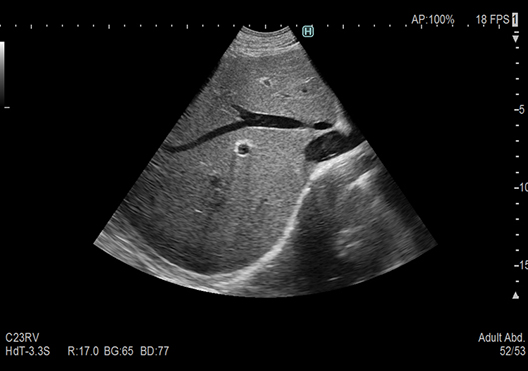

Images with "Clearer Visibility" are produced by our image processing technology that enhances tissue structure visibility. Realizes stable imaging with less patient dependency.

ON